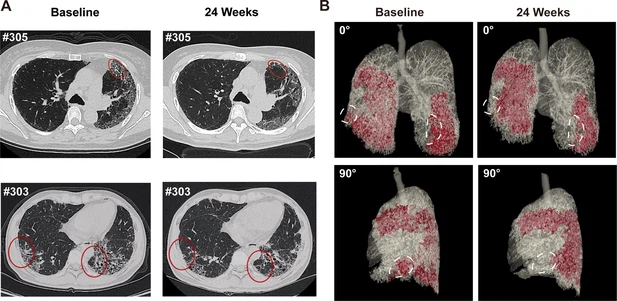

- 蜂窩狀病變消退:1M劑量組中兩名患者(#303、#305)的HRCT顯示下葉蜂窩狀病變減少(圖4A),三維重建證實下葉病變區(qū)域縮小(圖4B)。

(A) 患者#305和#303在基線和REGEND001治療后24周的代表性肺部CT圖像。紅色圓圈表示蜂窩狀病變消退。(B) 患者#305連續(xù)CT圖像的三維可視化。紅色區(qū)域表示細(xì)胞治療前后肺部受損區(qū)域(網(wǎng)狀和蜂窩狀)。白色圓圈表示下葉病變消退。

總結(jié):REGEND001高劑量治療可顯著改善IPF患者運動能力及生活質(zhì)量,并在部分患者中實現(xiàn)肺纖維化結(jié)構(gòu)的可逆性修復(fù)(尤其下葉)。療效呈現(xiàn)劑量依賴性,且與細(xì)胞分布機(jī)制相關(guān)。盡管樣本量有限,但結(jié)果為再生療法逆轉(zhuǎn)肺纖維化提供了首個影像學(xué)證據(jù),需擴(kuò)大隊列驗證長期效果及機(jī)制。